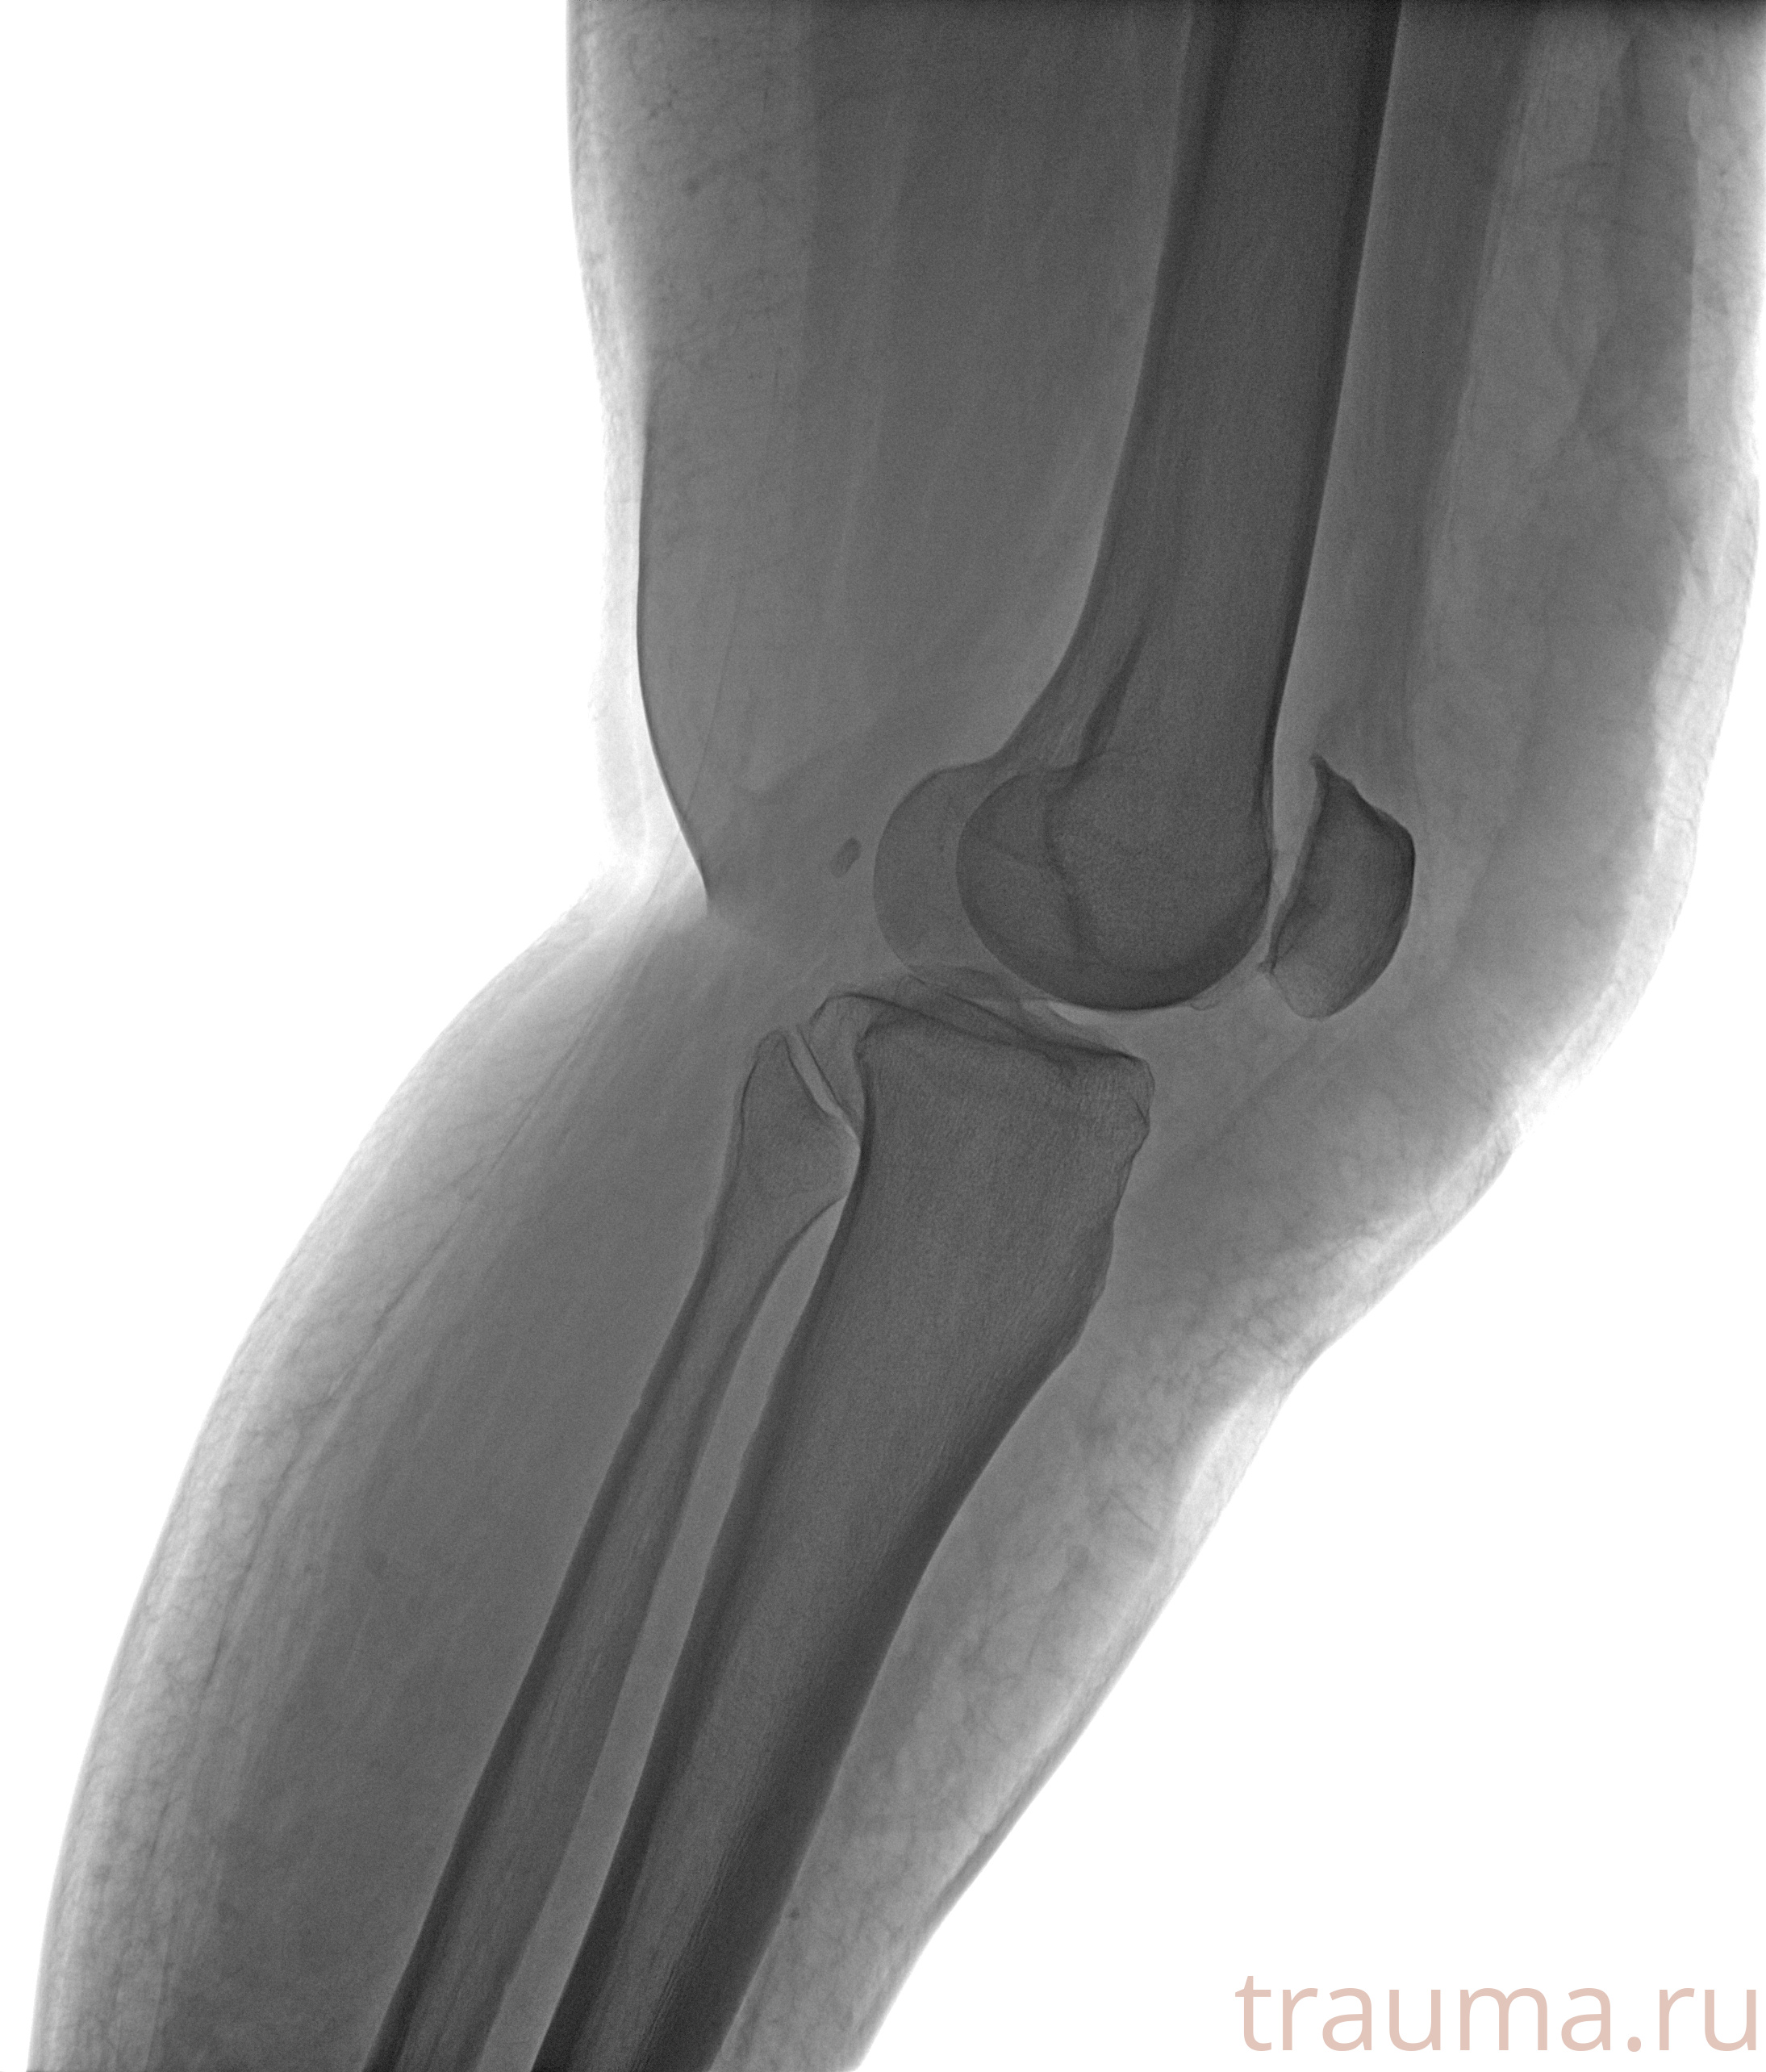

Рентгенограммы

Рентген на дому: по вашему адресу приезжает врач-рентгенолог, травматолог-ортопед с мобильным рентгеновским аппаратом, проводит диагностику травмы или заболевания, делает необходимые рентгенограммы, дает рекомендации по дальнейшему лечению. Получить качественные снимки в домашних условиях возможно благодаря уникальной методике, разработанной МосРентген Центром для института  Склифосовского